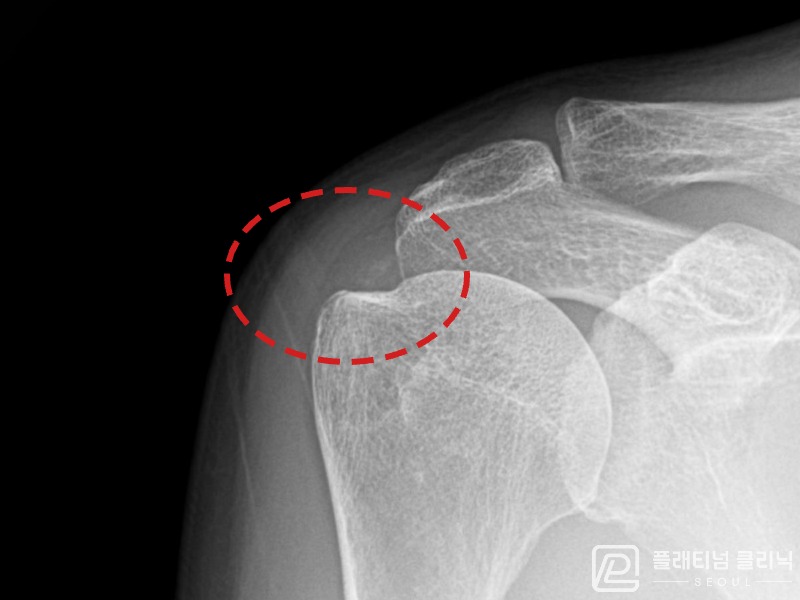

[촬영시기:21.08.30~21.09.09]

[석회분쇄흡입술] 우측 어깨 통증으로 밤잠을 못 이루고 팔을 올리기 어려워진 30대 여성 환자로, X-ray에서 우측 극상근건 내 석회 침착이 확인되어 석회분쇄흡입술을 시행하였습니다.